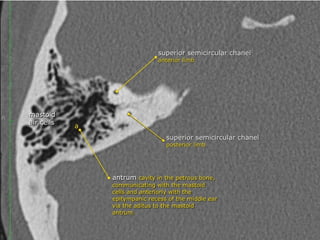

The semicircular canals

 are components of the bony labyrinth within the

 There are three semicircular canals on each side, each forming two

thirds of a full circle which are orientated perpendicular (at right

angles) to each other. They all open into the vestibule. They have

differing and variable lengths but uniform diameters of approximately

1 mm.

 Each semicircular canal has a dilatation termed ampulla at one end,

the posterior and superior semicircular canals share a common crus

formed by the fusion of the posterior crus of the superior semicircular

canal and the anterior crus of the posterior semicircular canal, which

then opens into the superomedial part of the vestibule, the lateral

semicircular canal, on the other hand, has two separate openings

into the vestibule

 Superior (anterior) semicircular canal (SSCC)

orientated in the vertical plane perpendicular (transverse) to the long axis of the

PTB. it lies under the arcuate eminence on the anterior surface of the PTB. Hair

cells of the superior semicircular duct supplied by the superior division of the

vestibulocochlear nerve (CN VIII). Seen perpendicular to long axis of

temporal bone

 Posterior semicircular canal (PSCC)

orientated in the vertical plane parallel to the long axis of the PTB

hair cells of the posterior semicircular duct supplied by the inferior division of CN

VIII

Lateral (horizontal) semicircular canal (LSCC)

orientated 30 degrees to the horizontal. shortest of the semicircular canals

hair cells of the lateral semicircular duct supplied by the superior division of CN

VIII.

Mastoid

 The antrum is a large aircell superior and posterior

to the tympanic cavity and connected to the

tympanic cavity via the aditus ad antrum.

 It is surrounded by smaller mastoid aircells.